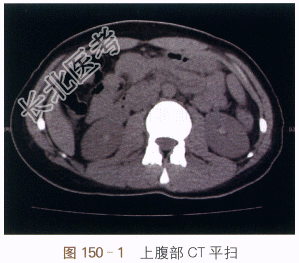

CT平扫(见图150-1)结肠肝区内可见软组织密度影,但无法与肠内容物分辨,很容易漏诊;增强CT(见图150-2)可见结肠肝区内侧管壁不规则增厚,动脉期可见多发迂曲血管显影,周围增厚的管壁轻度强化;选择性肠系膜上动脉造影(见图150-3)提示可见结肠肝区异常血管团、迂曲供血动脉及增粗的引流静脉,实质期可见圆形异常染色;内镜检查证实为肠壁息肉,表面可见出血(见图150-4)。